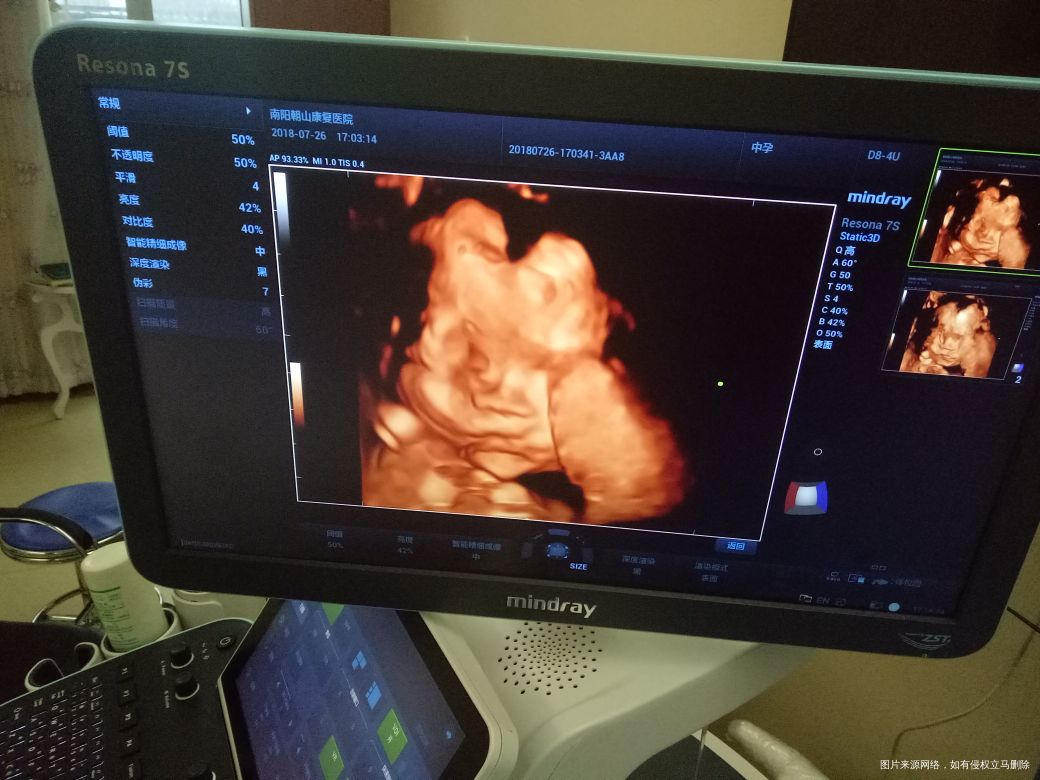

二胎四维图,大脸盘,大家猜猜是男是女,自己已知[开心]

这是报告单